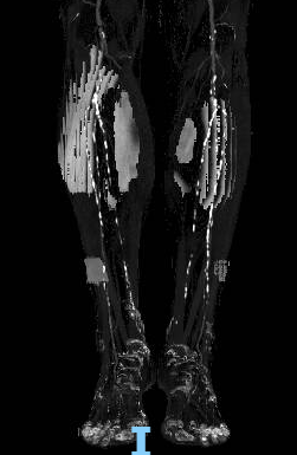

合并糖尿病,膝下动脉多发钙化、闭塞,远端流出道差

步进造影配合血管腔内超声诊断导管提示:股浅动脉全程、腘动脉、胫腓干动脉血流通畅,未见明显夹层、造影剂外溢,远端未见栓塞,膝下动脉如前。

腘动脉压力:90mmHg,比值0.73(原比值 0.54)

足背动脉压力85mmHg,比值0.69(原比值 0.45)

腘动脉压力:120mmHg,比值0.98 (原比值 0.65)

胫后动脉压力:118mmHg,比值0.96(原比值 0.54)

足背动脉压力:115mmHg,比值0.93(原比值 0.59)